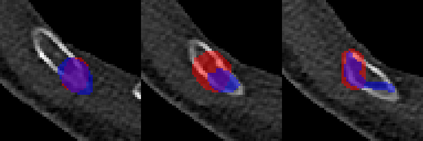

Rib fractures are a common and potentially severe injury that can be challenging and labor-intensive to detect in CT scans. While there have been efforts to address this field, the lack of large-scale annotated datasets and evaluation benchmarks has hindered the development and validation of deep learning algorithms. To address this issue, the RibFrac Challenge was introduced, providing a benchmark dataset of over 5,000 rib fractures from 660 CT scans, with voxel-level instance mask annotations and diagnosis labels for four clinical categories (buckle, nondisplaced, displaced, or segmental). The challenge includes two tracks: a detection (instance segmentation) track evaluated by an FROC-style metric and a classification track evaluated by an F1-style metric. During the MICCAI 2020 challenge period, 243 results were evaluated, and seven teams were invited to participate in the challenge summary. The analysis revealed that several top rib fracture detection solutions achieved performance comparable or even better than human experts. Nevertheless, the current rib fracture classification solutions are hardly clinically applicable, which can be an interesting area in the future. As an active benchmark and research resource, the data and online evaluation of the RibFrac Challenge are available at the challenge website. As an independent contribution, we have also extended our previous internal baseline by incorporating recent advancements in large-scale pretrained networks and point-based rib segmentation techniques. The resulting FracNet+ demonstrates competitive performance in rib fracture detection, which lays a foundation for further research and development in AI-assisted rib fracture detection and diagnosis.